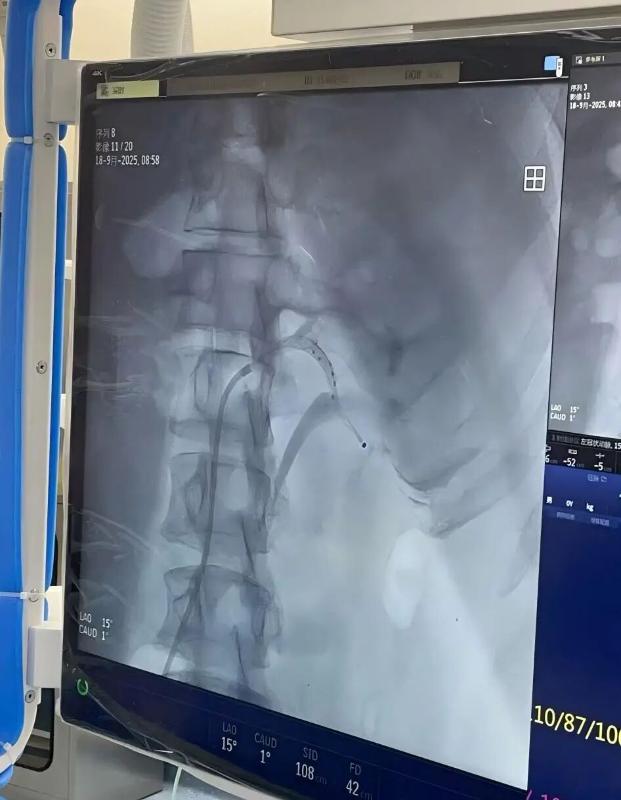

瑞金医院嘉定院区刘常远主治医师接诊后将其收入病房,在陈歆主任指导下对张先生进行了全面细致的评估,重点在于筛查继发性高血压及评估靶器官损害情况,最终诊断原发性高血压,结合患者肾动脉情况明确其符合RDN手术指征,完善术前检查后为其制定了周密的手术方案。手术当天,由许建忠主任作为主刀医师,刘常远主治医师、李明春主治医师作为助手,凭借娴熟的介入技术,将肾动脉消融导管精准送达双侧肾动脉及副肾动脉,通过射频能量对双侧肾动脉交感神经进行消融。整个手术历时约1.5个小时,共消融56个点位,全程患者无明显不适,术后在护理团队的精心照护下,患者生命体征平稳,感觉良好。

术后至今,张先生仅服用1种降压药物,血压逐渐下降并趋于稳定,头晕症状较前明显缓解,家庭自测血压平均126/85mmHg,心率78次/分。患者的术后情况也在持续随访中。